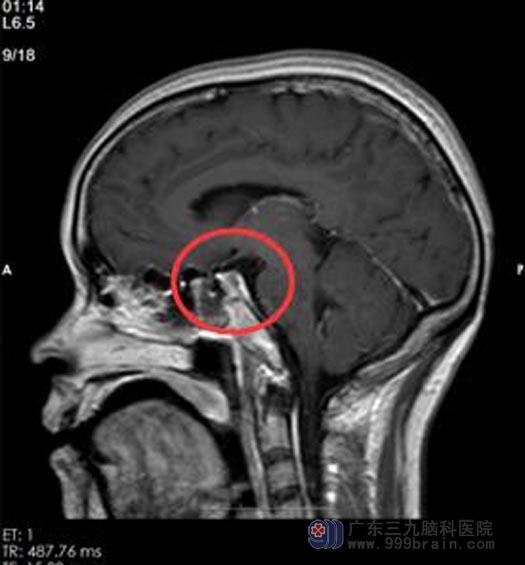

手术后,刘女士的各项生命体征平稳,头痛症状消失。从入院到康复出院只花了10天时间,这让她们一家人都非常开心。

手术后